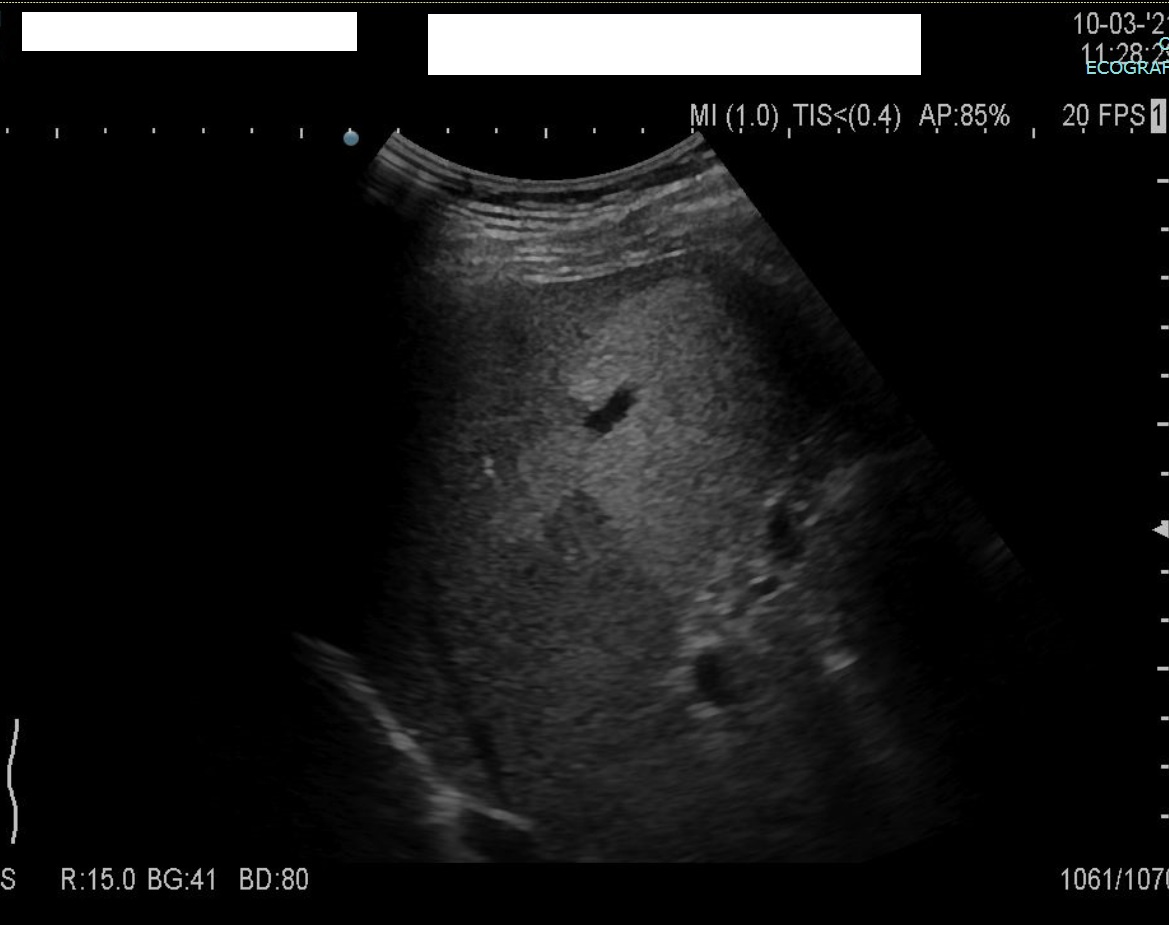

Below an example in a 53y man with large areas of focal steatosis results of massive portal thrombosis (Antiphospholipid syndrome).